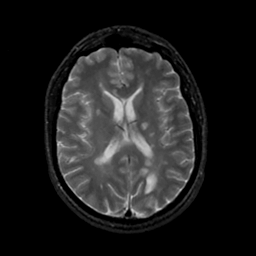

MR Study #18, July 21, 1991 -- Slice #29

[Home][Help][Clinical][Tour 1][Tour 2] Slice 29